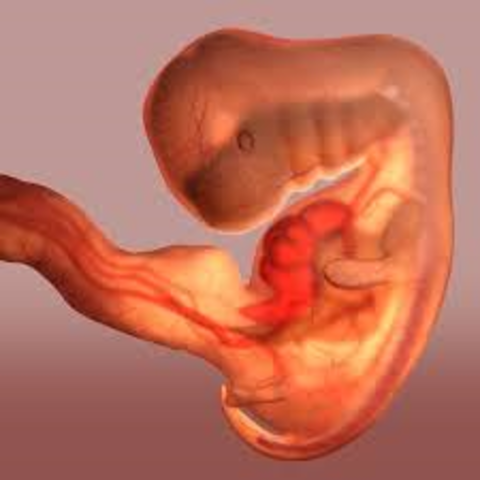

• Week 5

Week 5

The embryo now starts the process of shaping into a human. The placenta is developing and amniotic fluid begins to build up whcih will surround the fetus. The embryo is about 2-5mm.

• Week 6

Week 6

The embryo is beginning to form their main organs. The spinal cord begins to start closing, the brain begins to divide into its lobes, arms and legs are growing and the heart beat starts to play.